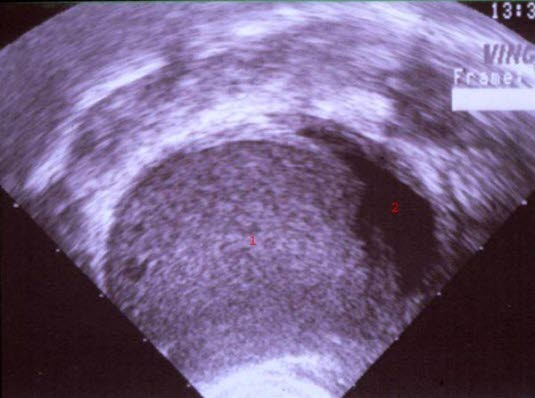

Endometriom

1. Endometrie-tumormasse

2. Uteruscavitet